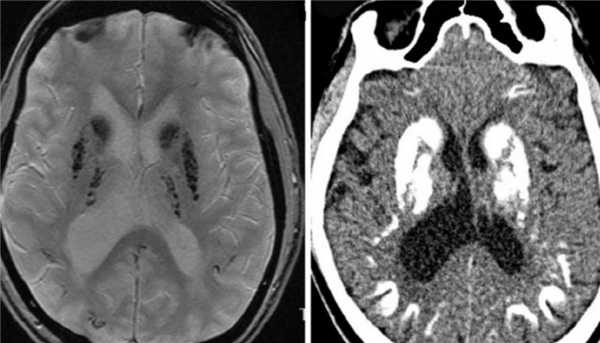

Синдромы Паркинсона включают группу заболеваний, близких по клинике к болезни Паркинсона. К синдромам Паркинсона относится быстро прогрессирующая деменция с тельцами Леви . При МРТ головного мозга низкий сигнал наблюдается не только от компактной части черного вещества, но и от скорлупы, которая становится даже темнее бледного шара. При оливопонтоцеребеллярной атрофии на сагиттальных МРТ головного мозга видно уменьшение объема моста и мозжечка. При прогрессирующем надъядерном параличе обнаруживается атрофия пластины четверохолмия. Описаны характерные симптомы при МРТ - «пингвина», «Микки Мауса» и другие, смысл которых заключается в описании признаков атрофии.

Прогрессирующий надъядерный паралич проявляется в виде нарушения взора вверх, экстрапирамидной симптоматики и умственных нарушениях. Заболевание развивается у лиц около 60 лет. Этиология неизвестна, почти все случаи спорадические. Частота 1-1,5 случаев на 100 тыс. населения. Заболевание характеризуется патологическим скопление в головном мозге тау-протеина. При МРТ головного мозга наблюдается диффузная атрофия, причем на сагиттальных Т1-взвешенных МРТ отмечается характерный симптом “пингвина”. Атрофические изменения моста и среднего мозга приводят к расширению водопровода и III желудочка, контур которых напоминает очертания пингвина.